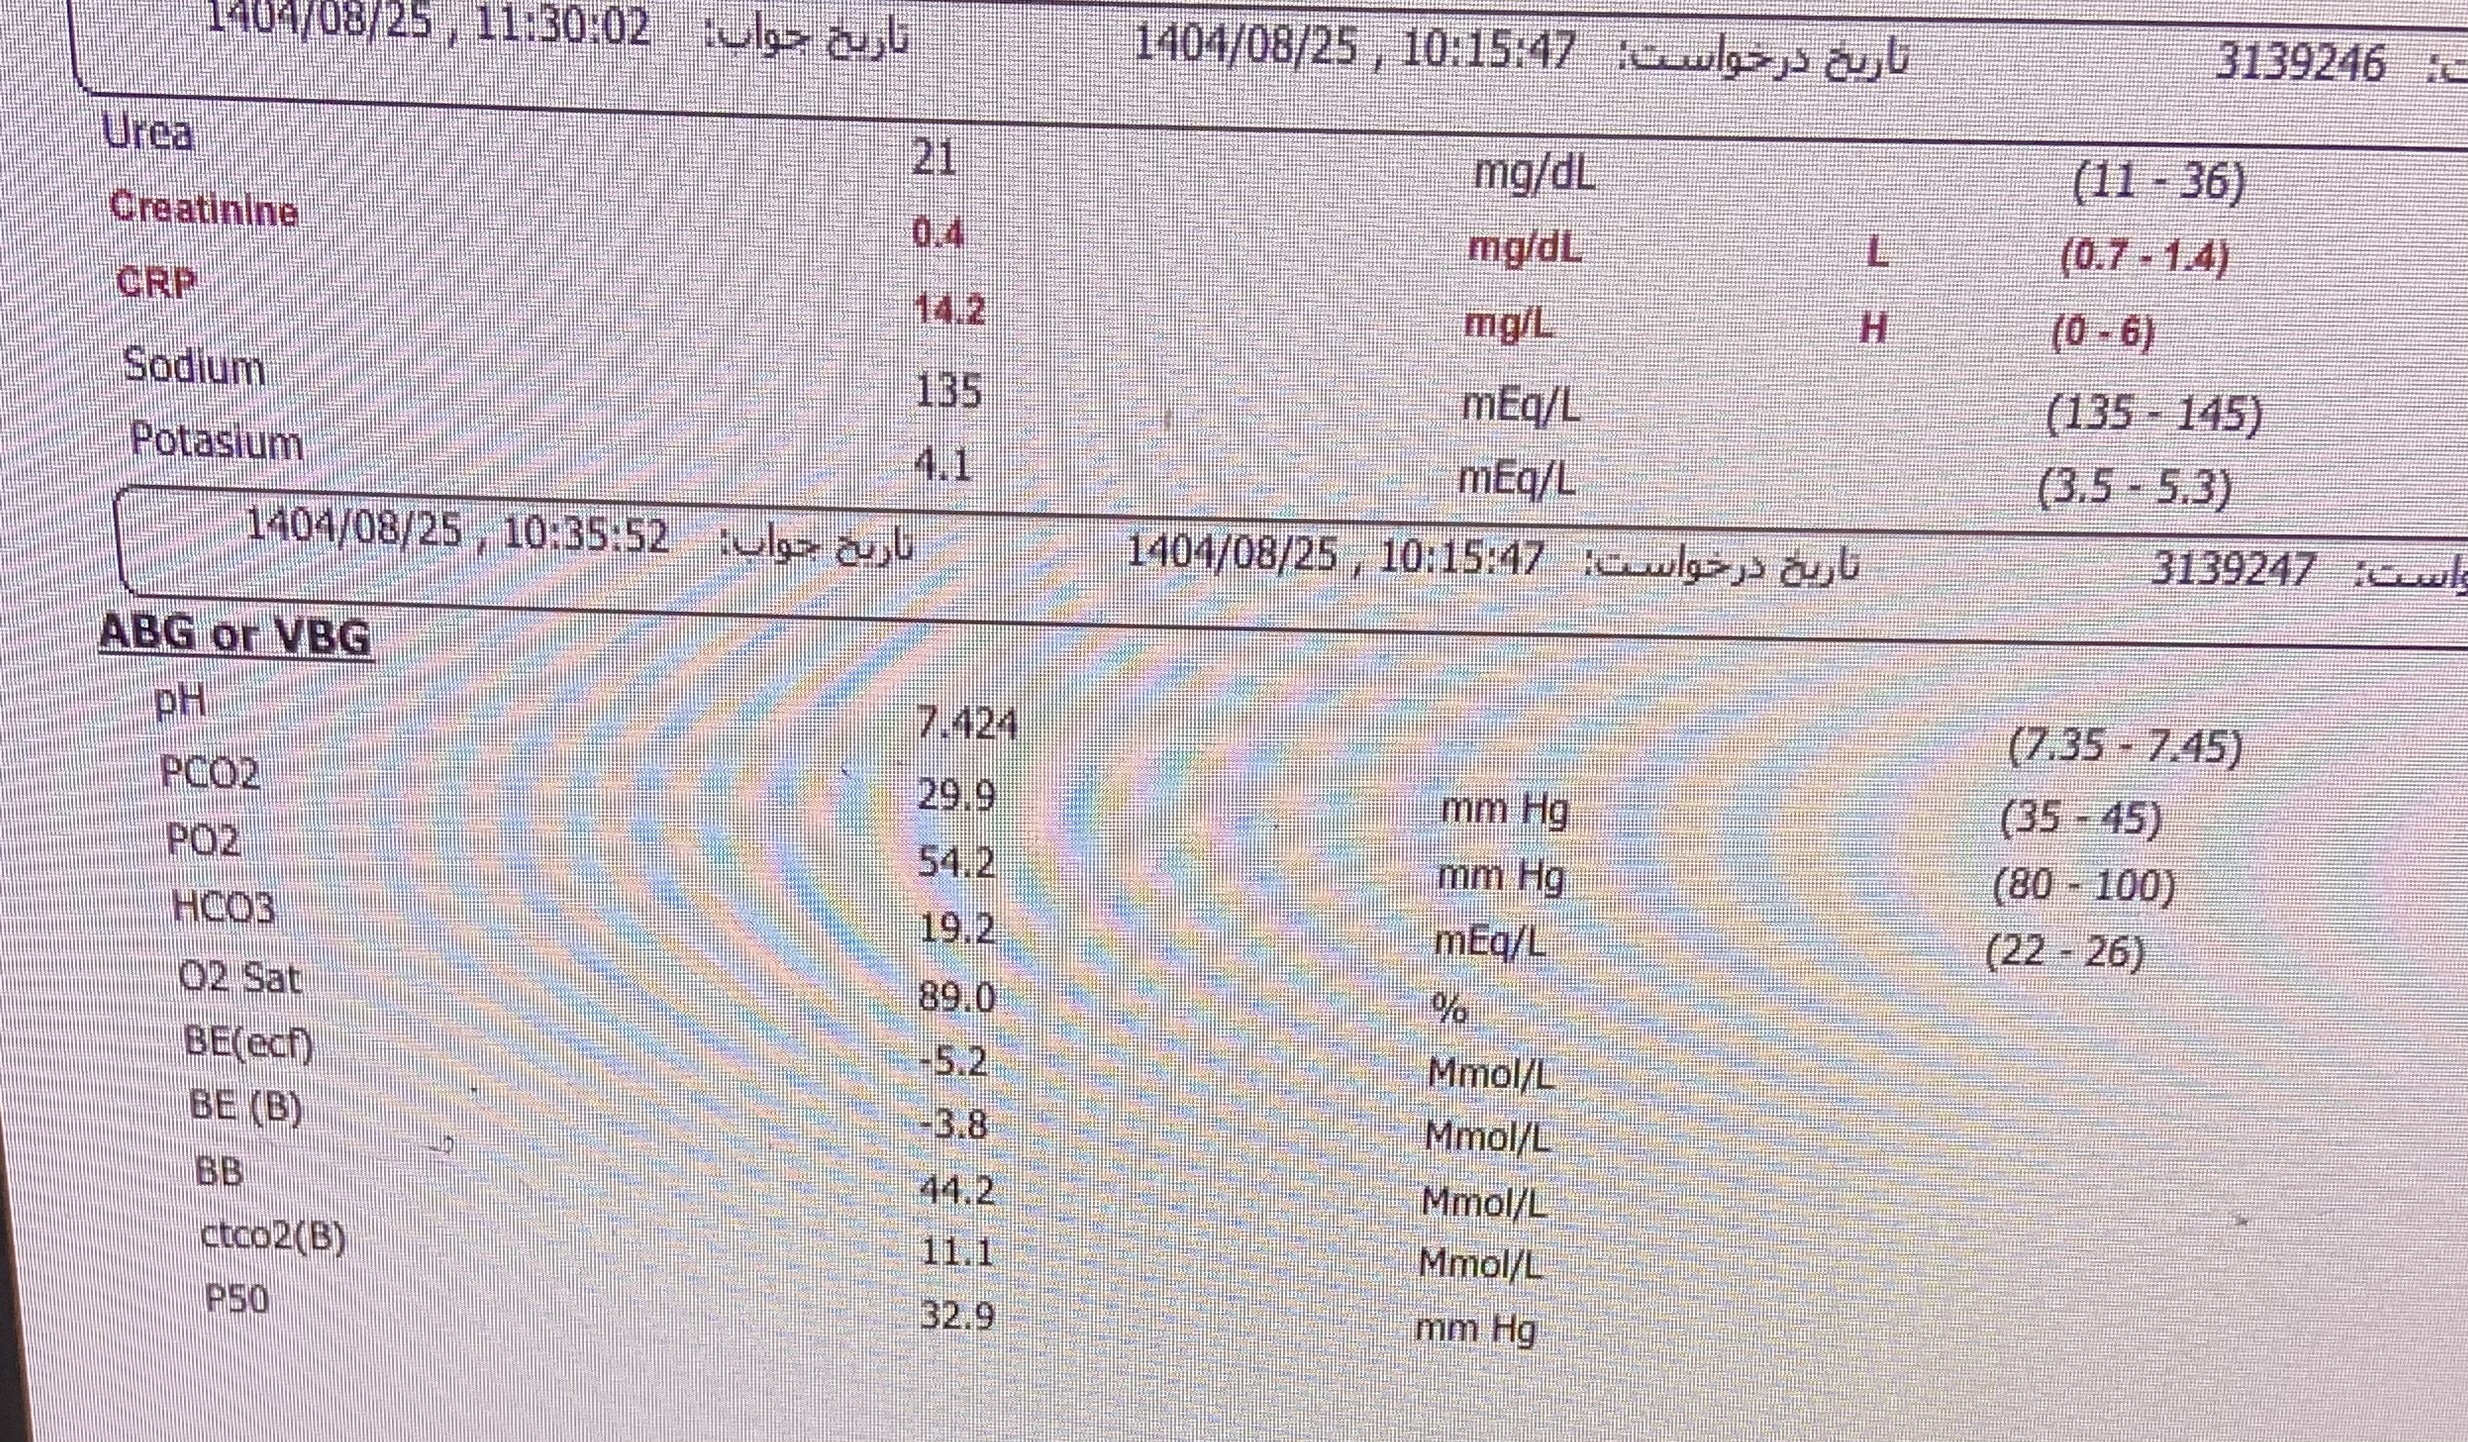

بیمار پسر ۲ سال ونه ماه مورد cah از ۱۷ روزگی تشخیص شده (با علایم اولیه poor feeding و تیرگی پنیس و لب وپتاسیم ۹ )با سرفه prوتب از دیشب شروع شده به اورژانس مراجعه کرده وهمچنین ۳ نوبت استفراغ داشته وابریزش بینی وسایقه بستری مکرر داشته با شک به گریز ادرنال بستری شدن

پسر 2ساله ونه ماه با تب وسرفه وابریزش و۳ بار استفراغ از دیشب به اورژانس مراجعه کرده مورد cah از ۱۷ روزگی تحت درمان با هیدروکورتیزون و فلودروکورتیزون بوده با شک به کریز ادرنال بستری شدن تاکی پنه وتاکی کاردی داشته

DDx

گریز ادرنال

پنومونی

گاستریت

سرماخوردگی

برونشیت

سپسیس